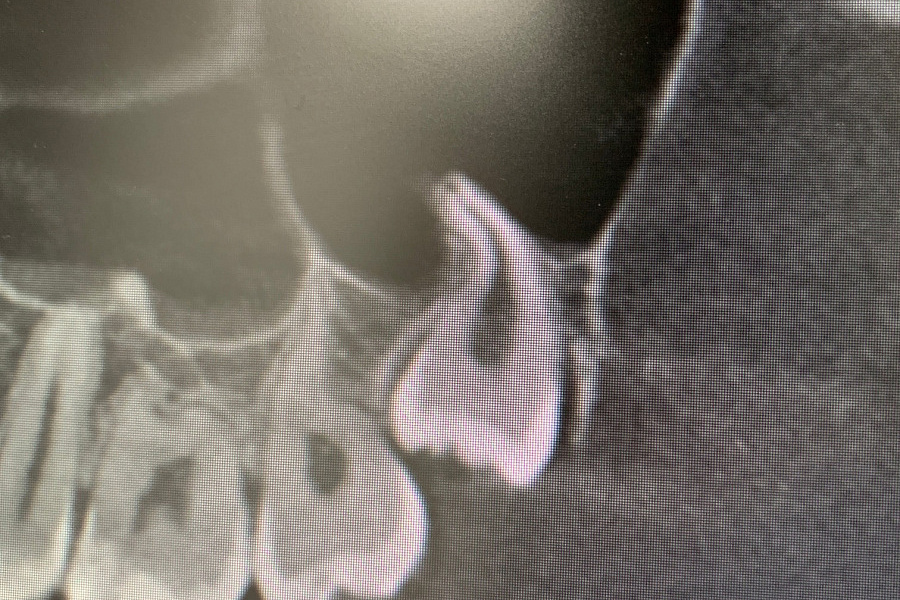

Удаление ретинированного дистопированного зуба мудрости на верхней челюсти слева.

Сложность данного кейса в том, что восьмой зуб упирается под углом в сторону седьмого зуба. Зуб удален полностью, дискомфорт пациент не испытывает.